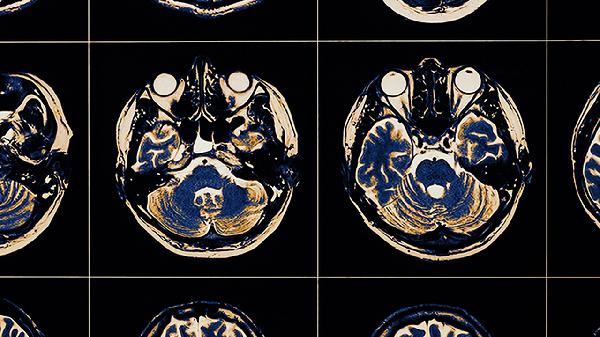

轻微的脑血栓一般不严重,但需要及时干预以防止病情进展。脑血栓的严重程度与血栓位置、大小及侧支循环建立情况有关,多数轻微脑血栓患者通过规范治疗可有效控制症状。